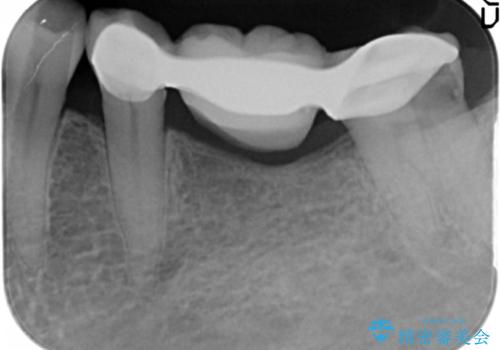

精査したところ、ブリッジの支台歯となっている左下の奥歯(左下7)は大きなう蝕により神経が死んでいました。

根管治療後、メタルボンドブリッジによる補綴治療を行いました。